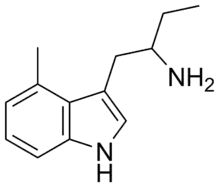

4-Methyl-αET | 1-(4-Methyl-1H-indol-3-yl)butan-2-amine | 28289-30-7 |

|